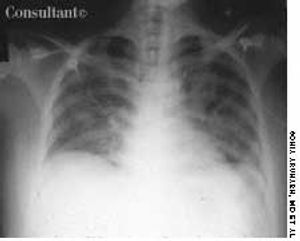

Having been treated for pulmonary tuberculosis (TB) 25 years earlier, a 60-year-old man (a nonsmoker) now complained of a chronic cough. The cough was occasionally accompanied by yellowish sputum but no hemoptysis. Examination revealed persistent coarse crackles in the right posterior hemithorax, and the x-ray study seen here established the diagnosis of cystic bronchiectasis.